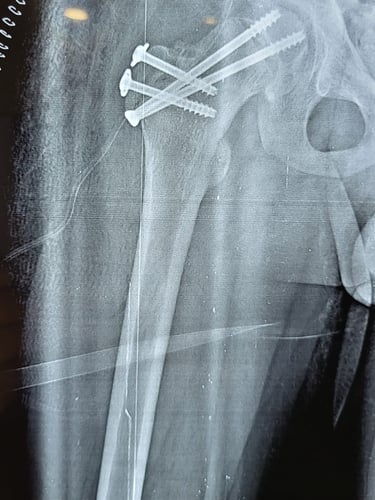

Sivam Hospital – Advanced Hip

Replacement In Chennai

At Sivam Hospital, we specialize in geriatric orthopedics, providing comprehensive care for bone and joint problems in elderly patients. Our orthopedic experts focus on treating age-related conditions such as fractures, arthritis, osteoporosis, and joint degeneration with safe and effective techniques.

We deliver personalized treatment from diagnosis to rehabilitation, making Sivam Hospital a trusted choice for elderly orthopedic care. With advanced facilities, minimally invasive options, and dedicated physiotherapy support, we ensure better mobility, reduced pain, and improved quality of life for senior patients.

👉 Why Choose Sivam Hospital Geriatric Orthopedics?

Expertise in Fracture Management, Arthritis & Osteoporosis Care

Specialized Joint Replacement & Trauma Care for Seniors

Modern Operation Theatres & Imaging Support

Compassionate Elderly-focused Rehabilitation & Physiotherapy

Safe, Reliable & Patient-Centered Orthopedic Care

Walk without pain. Trust Sivam Hospital for advanced hip replacement and a better quality of life.